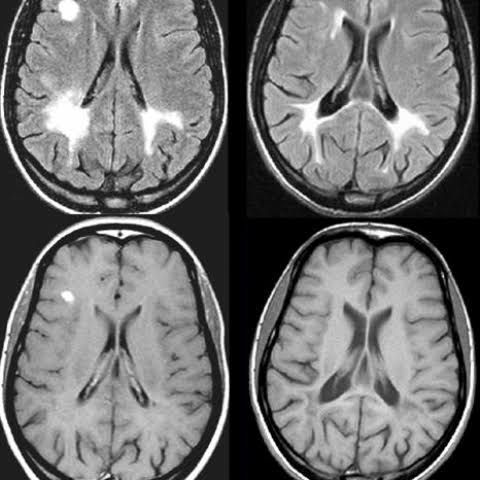

Causes of schilder's sclerosis

Doctors aren't sure what causes Schilder's disease. Because it usually starts when kids are so young, researchers think there may be a genetic link.